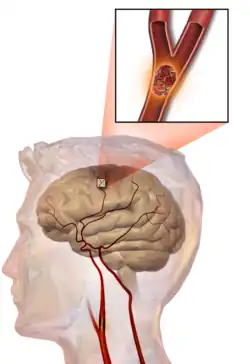

- ACV o ictus isquémico o infarto cerebral: una isquemia (disminución importante del flujo sanguíneo) en el cerebro, de manera anormalmente brusca; el flujo sanguíneo deficiente al cerebro termina produciendo muerte celular.[4]

Ictus isquémico

Un ictus isquémico o ataque cerebrovascular oclusivo, también llamado infarto cerebral, se presenta cuando la estructura pierde la irrigación sanguínea debido a la interrupción súbita e inmediata del flujo sanguíneo, lo que genera la aparición de una zona infartada y es en ese momento en el cual ocurre el verdadero infarto cerebral, y se debe solo a la oclusión de alguna de las arterias que irrigan la masa encefálica, ya sea por acumulación de fibrina o de calcio o por alguna anormalidad en los eritrocitos, pero generalmente es por arteriosclerosis (también ateroesclerosis, de ateroma) o bien por un émbolo (embolia cerebral) que procede de otra localización, fundamentalmente el corazón u otras arterias (como la bifurcación de la carótidas o del arco aórtico). La isquemia de las arterias cerebrales puede producirse por los siguientes mecanismos y procesos:

En un ictus trombótico o aterotrómbico, se forma un coágulo (trombo) en una de las arterias que irrigan el cerebro, lo que provoca la isquemia; este fenómeno se ve favorecido por la presencia de placas de aterosclerosis en las arterias cerebrales.

En el ictus trombótico, generalmente se forma un coágulo de sangre[25] alrededor de las placas ateroscleróticas. Dado que el bloqueo de la arteria es gradual, la aparición de accidentes cerebrovasculares trombóticos sintomáticos es más lenta que la de un ictus hemorrágico. Un trombo en sí (incluso si no bloquea por completo el vaso sanguíneo) puede provocar un ACV embólico si el trombo se rompe y viaja por el torrente sanguíneo, momento en el que se denomina émbolo. Dos tipos de trombosis pueden causar un accidente cerebrovascular:

Ictus embólico

Es consecuencia de un coágulo formado en una vena de otra parte del cuerpo (émbolo) y que, tras desprenderse total o parcialmente, viaja hacia el cerebro a través del torrente sanguíneo. También puede deberse a otro material llegado al torrente circulatorio por diferentes motivos. Habitualmente es un coágulo formado en el corazón, o también una fractura (embolismo graso), un tumor (embolismo metastásico), un fármaco o incluso una burbuja de aire. Al llegar a las pequeñas arterias cerebrales, el émbolo queda encallado cuando su tamaño supera el calibre de estas, dando lugar al fenómeno isquémico.